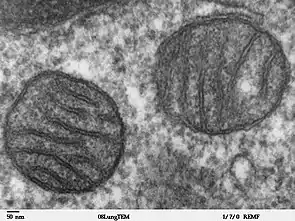

Mitochondrial DNA mutations

Mitochondria are essential organelles in eukaryotic cells. Their function is to convert the potential energy of glucose, amino acids, and fatty acids into adenosine triphosphate (ATP) in a process called oxidative phosphorylation. Mitochondria carry their own DNA, called mitochondrial DNA (mtDNA). The information stored in the mtDNA is used to produce several of the enzymes essential to the production of ATP.[1]

Between 20 and 25 percent of Leigh syndrome cases are caused by mutations in mitochondrial DNA. The most common of these mutations is found in 10 to 20 percent of Leigh syndrome and occurs in MT-ATP6, a gene that codes for a protein in the last complex of the oxidative phosphorylation chain, ATP synthase, an enzyme that directly generates ATP. Without ATP synthase, the electron transport chain will not produce any ATP.[1] The most common MT-ATP6 mutation found with Leigh syndrome is a point mutation at nucleotide 8993 that changes a thymine to a guanine. This and other point mutations associated with Leigh syndrome destabilize or malform the protein complex and keep energy production down in affected cells.[9] Several mitochondrial genes involved in creating the first complex of the oxidative phosphorylation chain can be implicated in a case of Leigh syndrome, including genes MT-ND2, MT-ND3, MT-ND5, MT-ND6 and MT-CO1.[7][10]